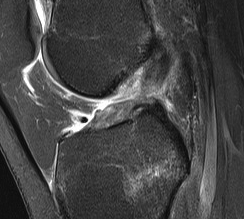

T2 weighted films

- fluid has a bright signal

- Highlights pathology / fluid